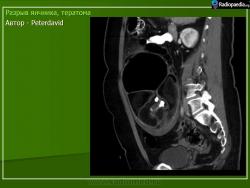

2.

Из литературных источников.

Зрелая тератома является доброкачественной опухолью и метастазов, как правило, не дает, хотя имеются единичные сообщения об имплантации опухоли по брюшине при разрыве тератомы яичника.